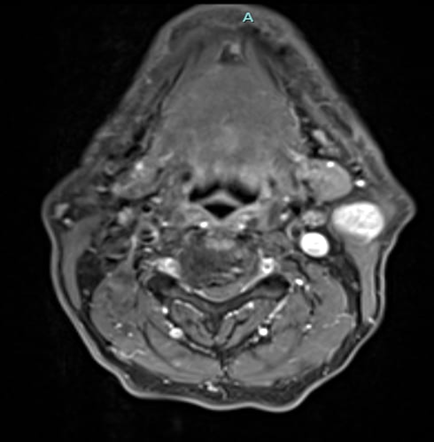

A 69-year-old male noticed a small painless lump in his left parotid region while shaving, Ultrasound examination of the area demonstrated a well-defined lesion measuring approximately 1.7x1.5 cm with internal vascularity, inseparable from the left parotid tail. The rest of the neck ultrasound was unremarkable; MRI was recommended to better define the lesion's origin before histopathological assessment. MRI revealed an oval-shaped, well-defined solid mass lesion in the left parotid gland, measuring about 2.2x1.9x1.3cm in maximum craniocaudally, transverse, and AP dimensions. The lesion is seen as separable from the deep part of the parotid gland, extending posteriorly, abutting the anterior aspect of the related sternomastoid muscle without definite muscle invasion. The lesion eliciting low signal in T1, heterogeneous low signal in T2 weighter images with heterogeneous post contrast enhancement. The main differential diagnoses considered were pleomorphic adenoma and Warthin tumor, although other possibilities could not be totally excluded. Surgical excision was performed. Histopathological analysis revealed Kaposi sarcoma within an intra-parotid lymph node. The lesion was excised with a margin of 0.5 cm. Although the findings were most consistent with a primary nodal Kaposi sarcoma, metastasis from other sites, particularly the skin, should be excluded (Table 1 and Figures 1-4).

Figure 3: MRI Finding of left parotid gland.